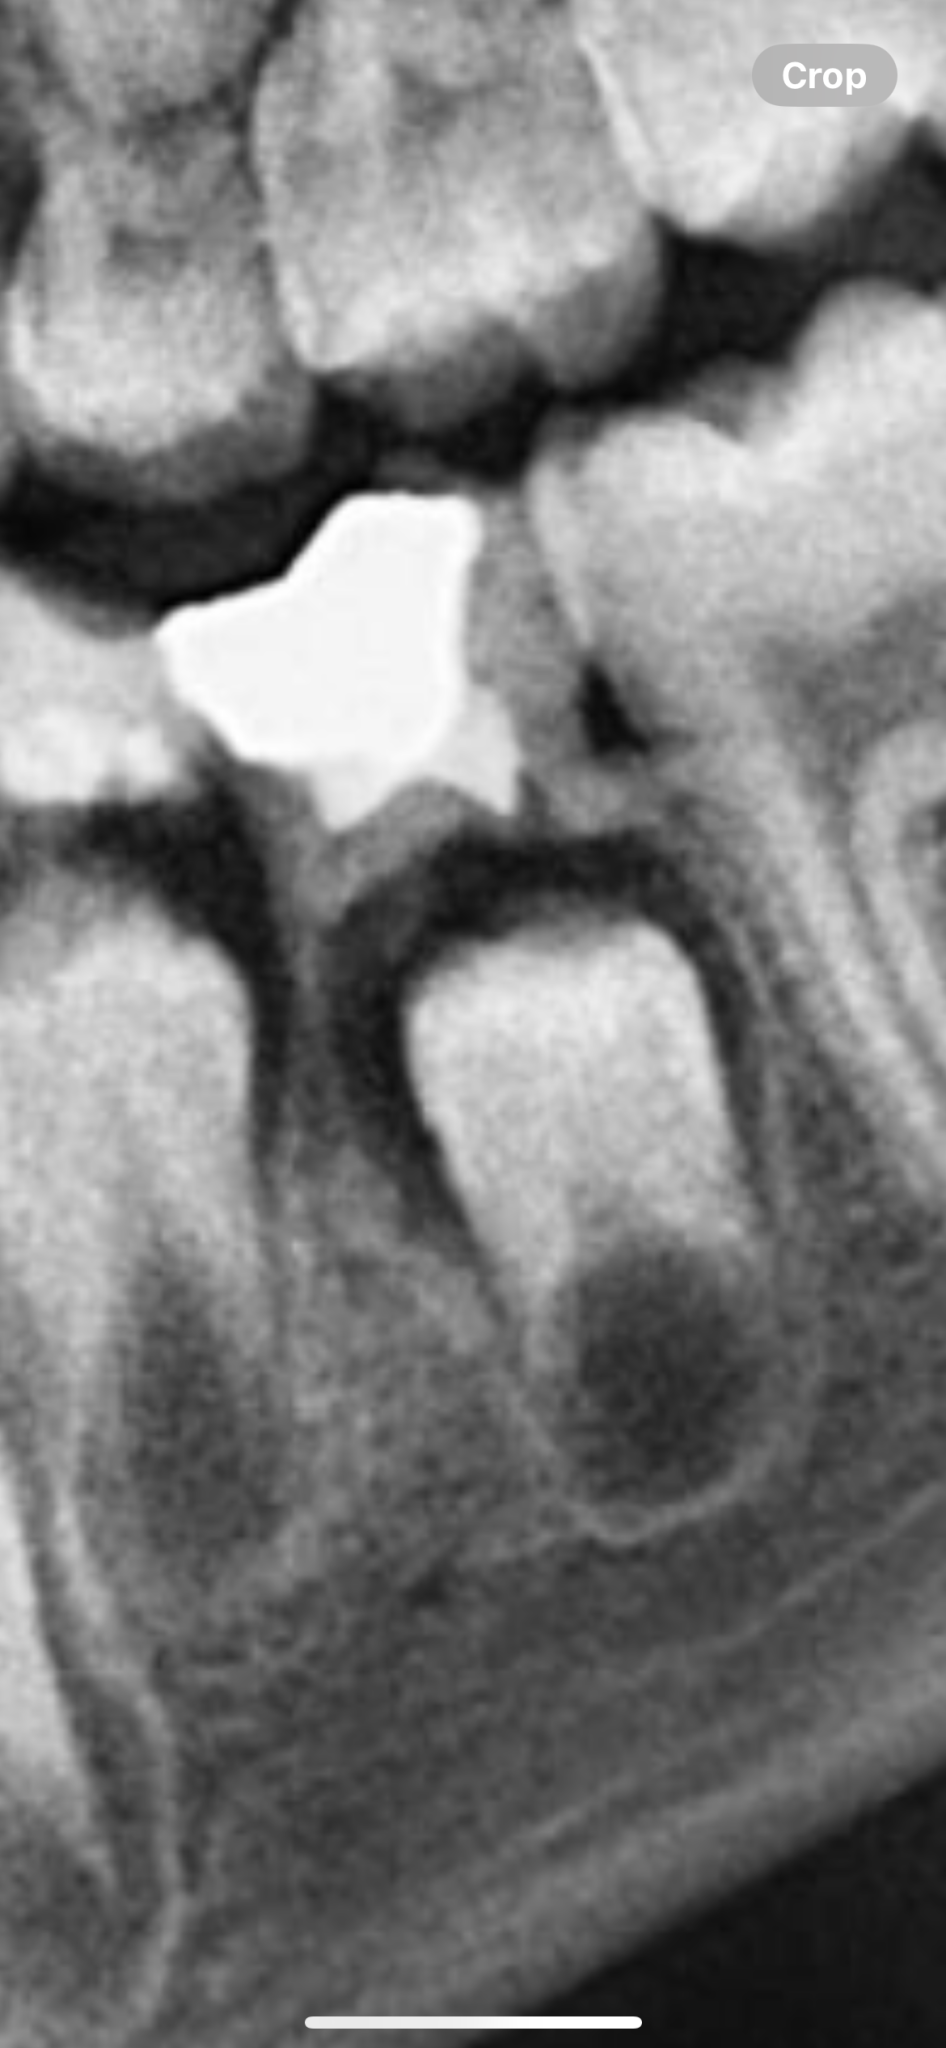

Вие сама си отговаряте на въпроса. Когато е "чист циркониева корона", цветът е еднотипен, по- плътен, а цветовете по зъбите преливат, ако се загледате и за да се постигне подобен ефект зъботехниците наслагват слоеве керамика, образно. На снимката е материал циркониева плочка